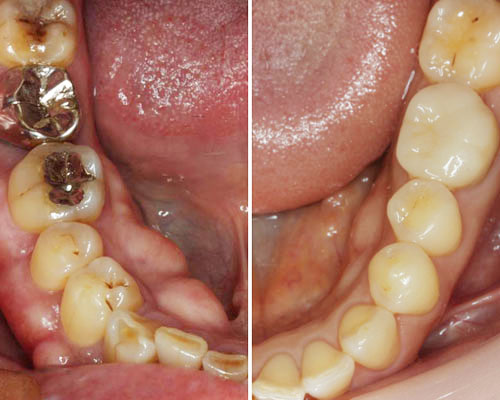

骨の出っ張り

皆さんも鏡でお口の中を確認してみて下さい。舌の下に豆のような出っ張りが左右対称にありませんか?写真の右が正常、左が「外骨症」と呼ばれる骨隆起です。よく見かける症状で悪いものではありませんが・歯ぎしりや食いしばりが原因だと言われています。